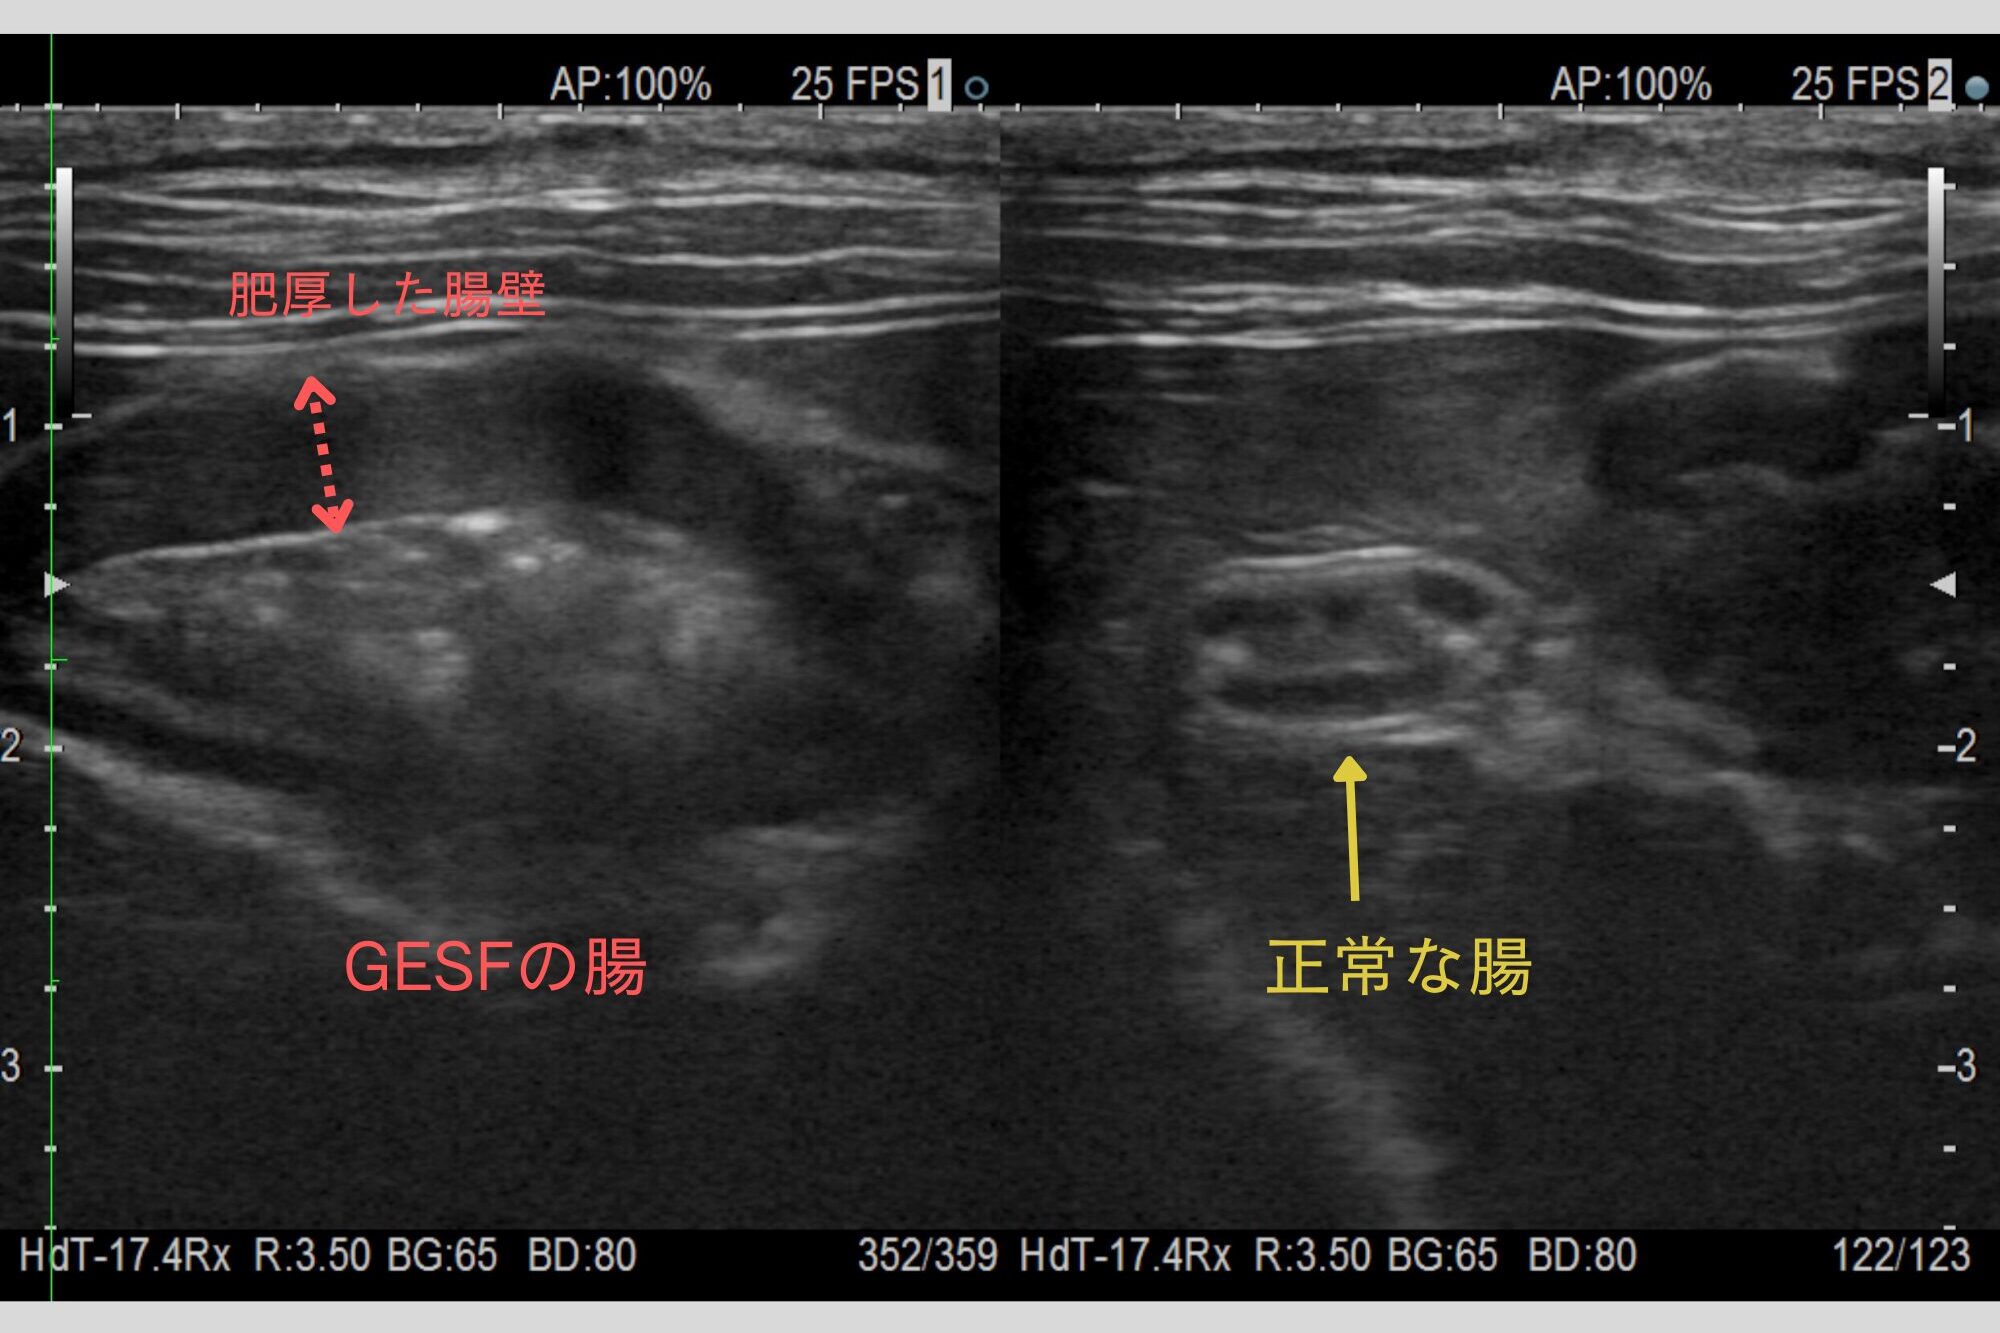

腸の病変は超音波検査で確認できます。多くの場合、腸の1か所が丸く腫瘤状に腫れ、近くのリンパ節も腫大しています。